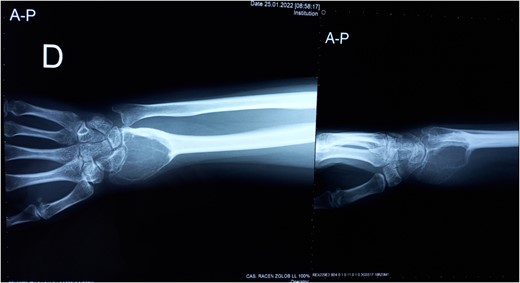

At 2 years follow-up, no clinical and X-ray signs of tumor recurrence or graft resorption were detected, both X-ray and CT confirmed that bone healing has been achieved (Figs 7 and 8) On physical examination, the patient has decreased wrist dorsal and palmar flexion, all other wrist movements are in normal range of motion and without pain (Fig. 9).

Follow-up X-ray of the right forearm 2 years after the surgery in profile plane

Follow-up X-ray of the right forearm 2 years after the surgery in anterior–posterior plane.